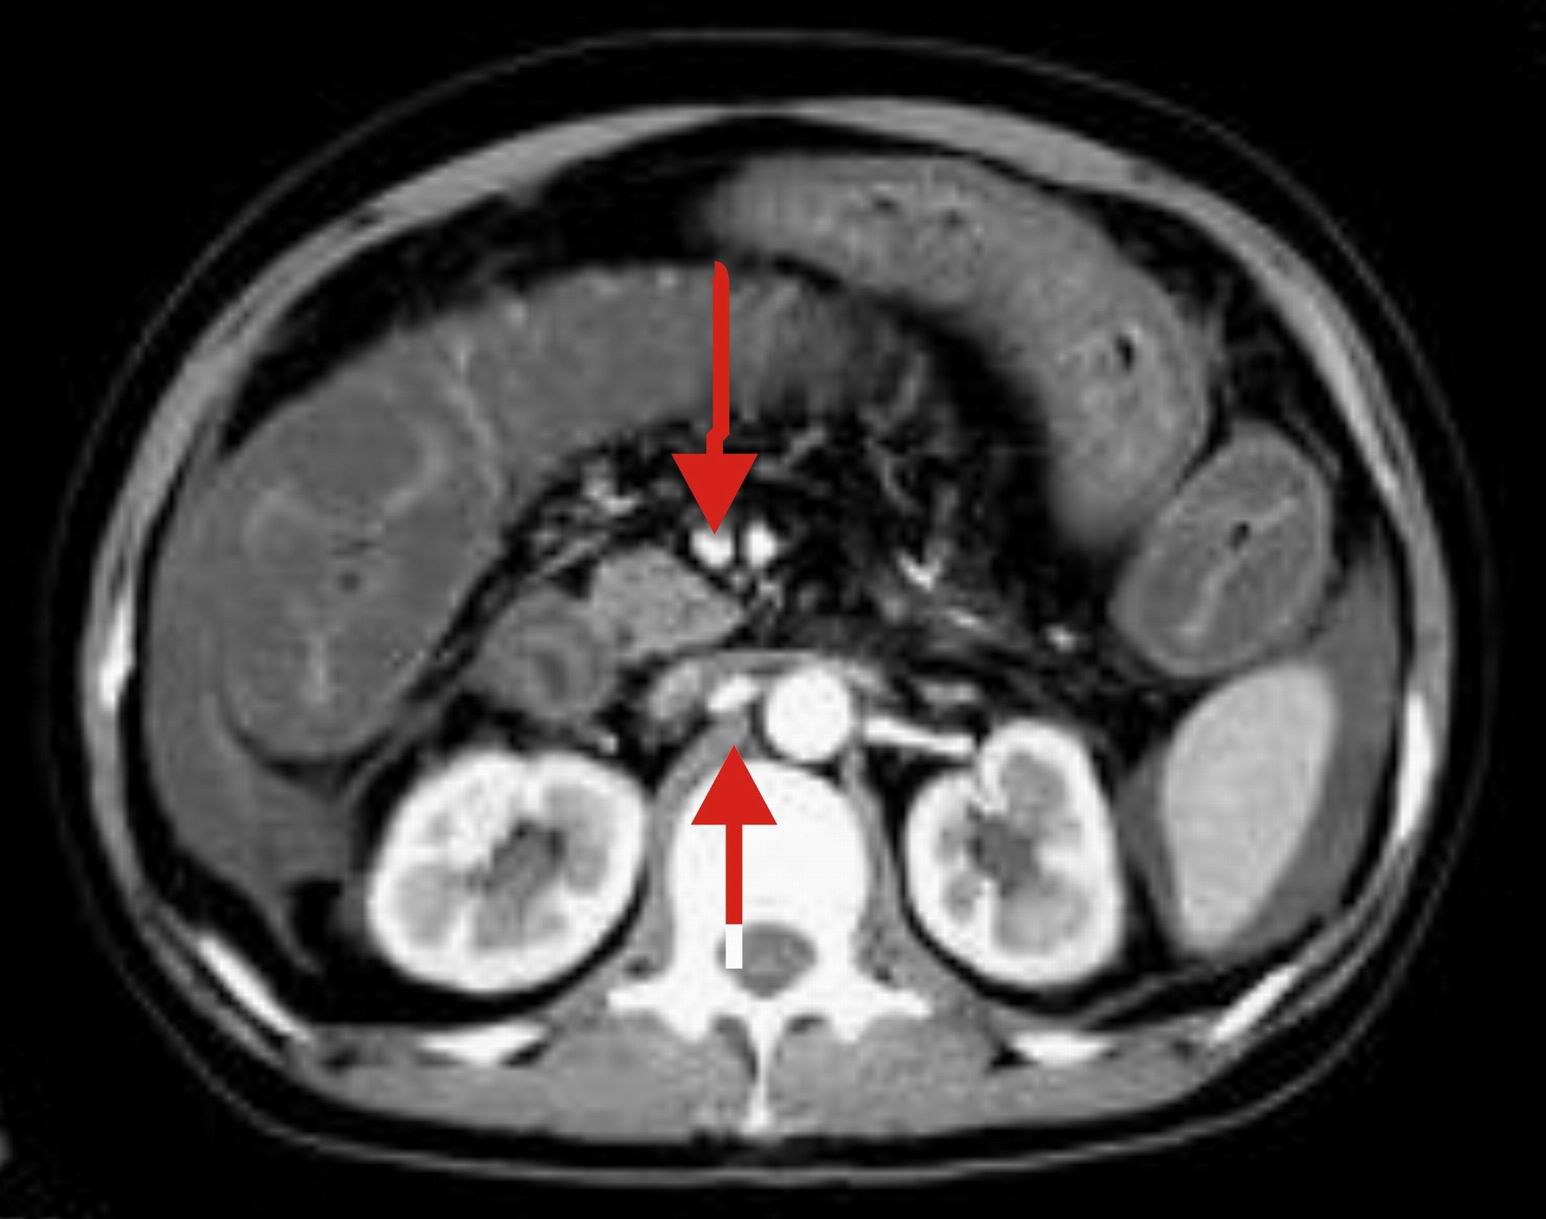

楼主上传图像很漂亮。把每幅图像放大,增强扫描,发现肠系膜上静脉管腔变形,其内见半圆形等密度影,结合病史,考虑肠系膜上静脉栓塞并肠壁间水肿,腹水。(这是首次发的话题)

今天这病例虽然公布了结果,但什么原因造成的肠道广泛性肠壁水肿还未知。今天,我特意把该病例的肠系膜上静脉的半圆形“充盈缺损”的图片做了图示,请网友们看。 在网上下载了一些资料,请大家分析。

我认为是sle所致的血管炎而形成的肠系膜上静脉吸附的“半圆形”栓子,造成肠系膜血管内的血液回流受阻或通而不畅所致肠道广泛性肠壁间水肿、腹水。

这个病例有脱发的病史,后转到风湿科,确诊为sle,经过一段时间的激素治疗,病情好转,以下是今日复查的ct